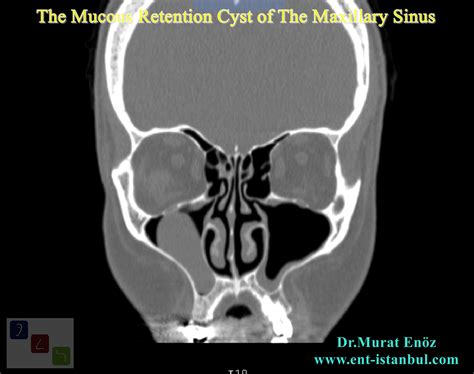

• Maxillary Sinus: Frequently discovered incidentally during routine dental X-rays or sinus scans.

In the sinuses, these are often referred to as antral pseudocysts. Unlike true cysts, which are lined with epithelial cells, many of these are "pseudocysts," meaning they lack a true cellular lining but function similarly in terms of fluid retention.

Maxillary Sinus Cysts:

• Usually produce no symptoms at all.

• They do not typically cause facial pain or pressure unless they grow exceptionally large.

• Often identified as a soft-tissue opacity on panoramic X-rays.

Visual Detection Visible to the naked eye Requires X-ray or CT scan

For sinus-related cysts, diagnosis is almost always incidental. If your doctor finds a "shadow" on your X-ray, they may recommend a follow-up CT scan to differentiate the cyst from a solid tumor or a localized polyp. Because these cysts are common, medical professionals are generally very adept at distinguishing them from more concerning growths.